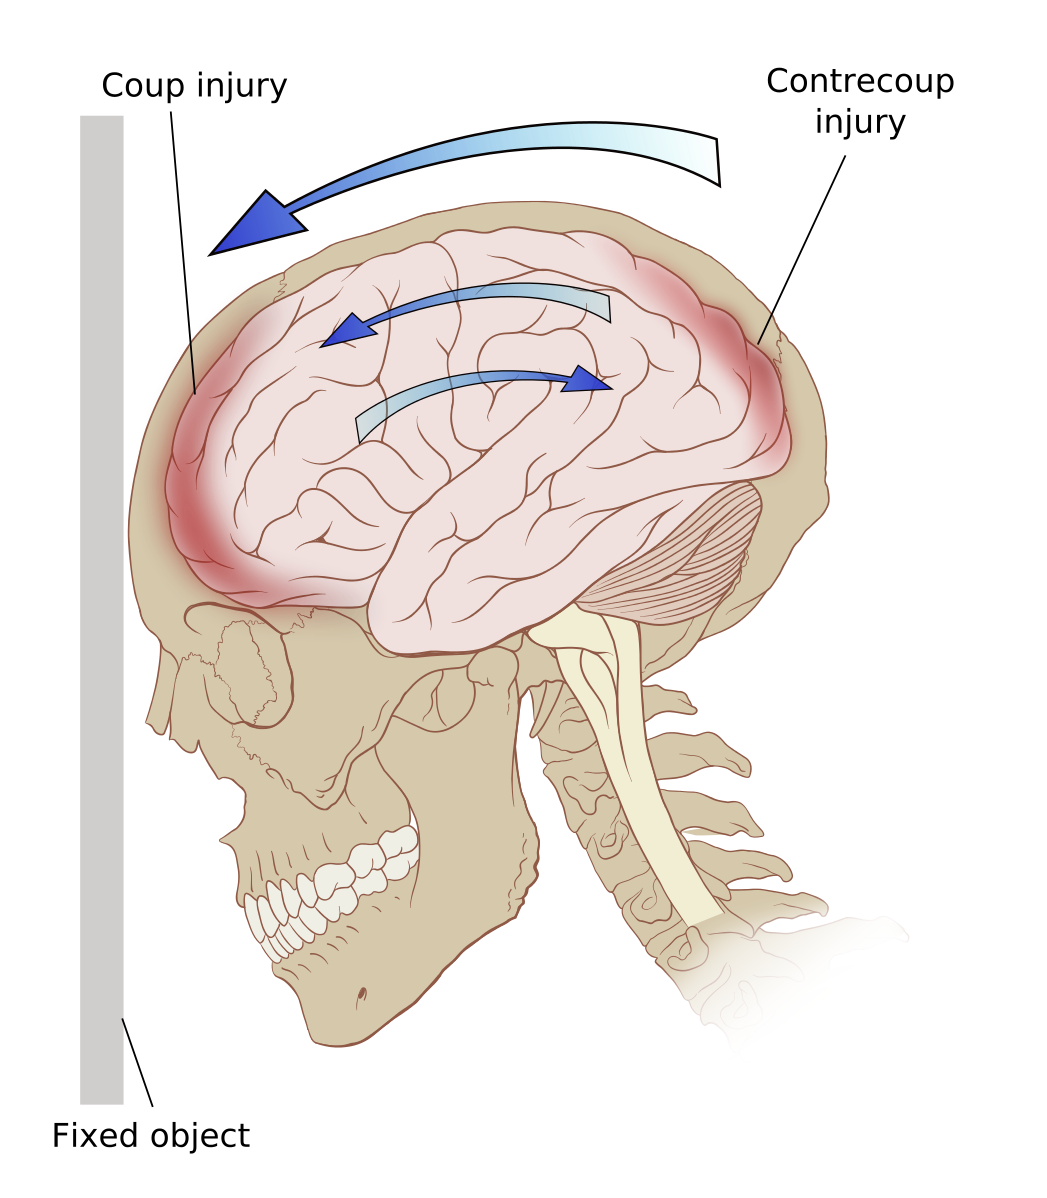

Active otorrhagia from the left ear Figure 2: Dead leech after removal - Contrecoup injury

Contrecoup

Coup Injury.